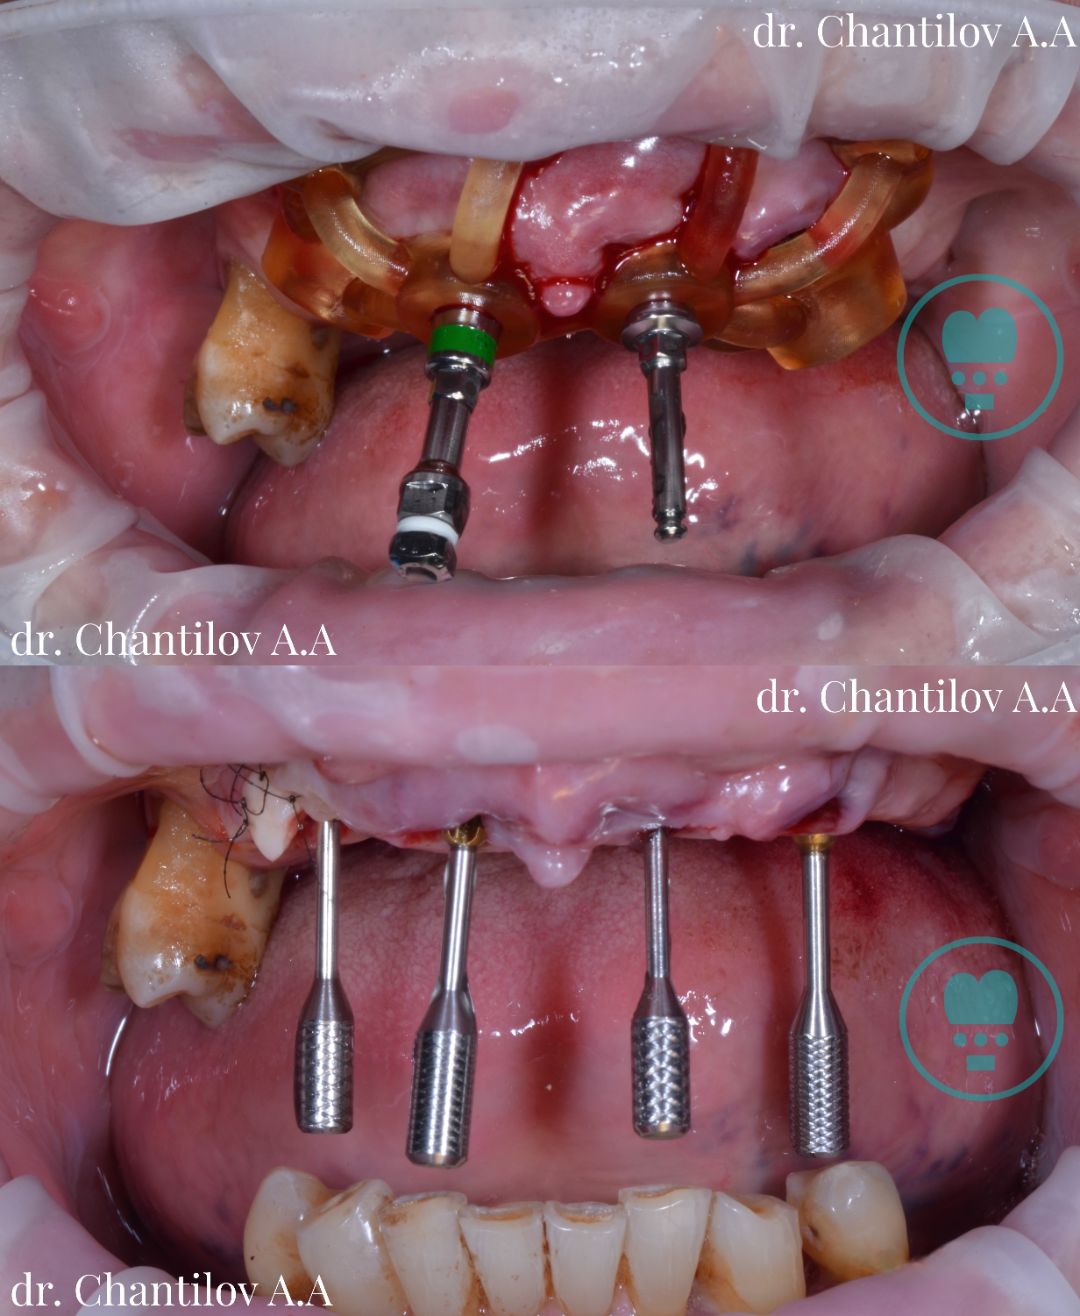

Имплантация зуба

Имплантация зубов челюсти - фото до и после

Изготовление индивидуального шаблона